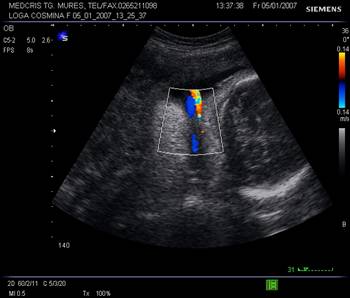

Arterele spiralate si placentomul. Dupa 28 sapt. mici ecouri anecogene rotunde apar in substanta placentara, reprezentand centrul placentomului - mica unitate de flux, unde se deschid artere spiralate. Cu ajutorul Doppler-ului color se poate urmari ejectia sangelui din arterele spiralate.

Vascularizatia uterina crescuta in trim. III, in peretele uterin nu trebuie confundata cu un hematom retroplacentar.

Fig nr.213 Vascularizatie a peretelui uterin subplacentara, ce nu trebuie confundata cu hematomul retroplacentar